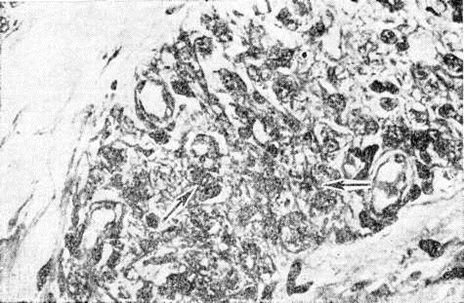

Рис. 6.

Микроскопическая картина кожного инфильтрата пограничного типа лепры: субэпидермальная зона свободна, инфильтрат состоит из слабо дифференцированных эпителиопдных клеток и лимфоцитов; 1 — эпидермис, 2 — субэпидермальная зона, 3 — инфильтрат. Окраска гематоксилин-эозином; × 120.

Рис. 7.

Микроскопическая картина характерного поражения нерва кожи (расслоение и инфильтрация периневрия) при погранично-лепроматозной лепре: I — нервный стволик, 2 — периневрий. Окраска гематоксилин-эозином; × 300.

Рис. 1—6.

Микроскопические картины поражений при различных формах лепры.